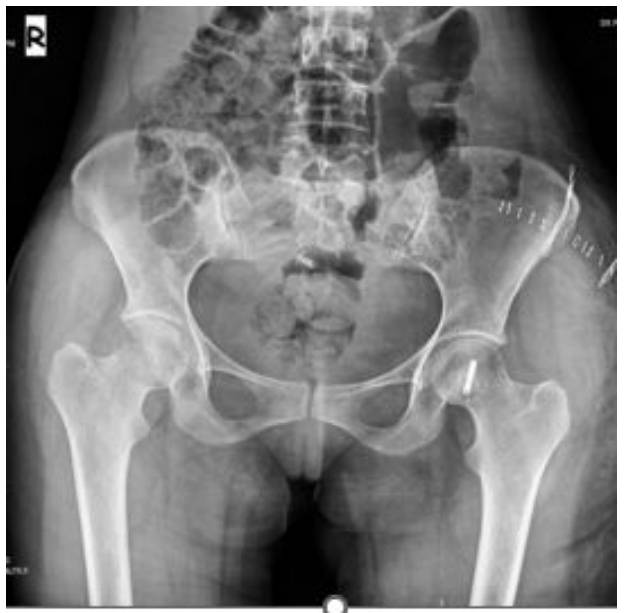

Post-Surgery: The X-ray shows that after tumor removal, the resulting cavity was filled with bone cement and fixed with a headless screw.